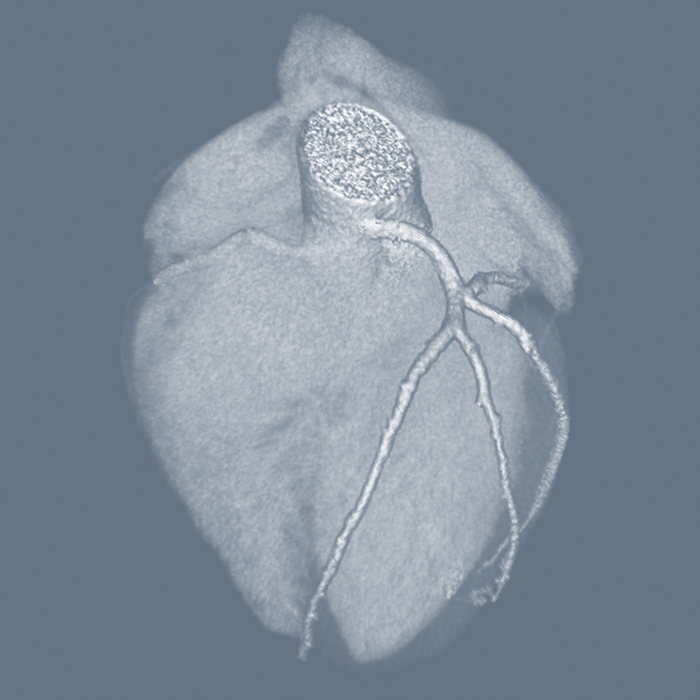

The last twenty years have seen a rapid development of cardiovascular imaging with advances in CT (Computed Tomography), MRI (Magnetic Resonance Imaging), and PET-CT with continued development in echocardiography and invasive angiography. This platform describes the different clinical cardiac presentations and the best use of the different imaging techniques for these presentations discussing their strengths and limitations based on the current evidence base.

The project is led by Dr. Tarun K Mittal, Consultant Cardiac Radiologist at the Royal Brompton and Harefield NHS Foundation Trust in London, UK with a contribution by experts in cardiology, cardiac surgery, imaging, and medical physics. The clinical and cardiac CT resources are being developed first with others following in due course. The platform is open to anyone who is interested in learning about cardiovascular imaging.